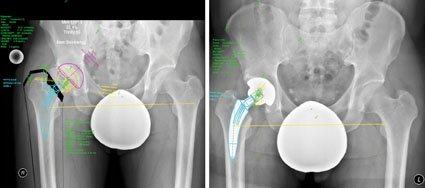

Es wurden 22 Fälle bei 18 Patienten (7 Frauen und 11 Männer) mit einer MiniHip versorgt. Jeweils 2 Männer und Frauen wurden beidseits versorgt. Die Nachuntersuchungszeit betrug 8,4 (±4,1) Monate. Das OP-Alter lag bei 58,5 (±8,4) Jahren und der Body Mass Index (BMI) bei 26,5 (±3,3). Ein Fallbeispiel inklusive prä- und postoperativer Planung mit biomechanischer Analyse zeigt die Abb. 1.

Die Schmerzwerte verringerten sich hochsignifikant ebenso wie alle Skalen des WOMAC. Der BLB-Score im Fallbeispiel (Abb. 1) verbesserte sich in der Op- Planung vom Ausgangsbefund 3 präoperativ auf 11 Punkte. Postoperativ wurde der Idealwert von 12 Punkten erreicht. Die Ergebnisse des BLB-Scores für die Gruppen sind in Abb. 3 dargestellt. Die Werte für die MiniHip-Gruppe liegen prä- und postoperativ über denen der Standard-Gruppe, ohne dass ein signifikanter Unterschied nachweisbar war.